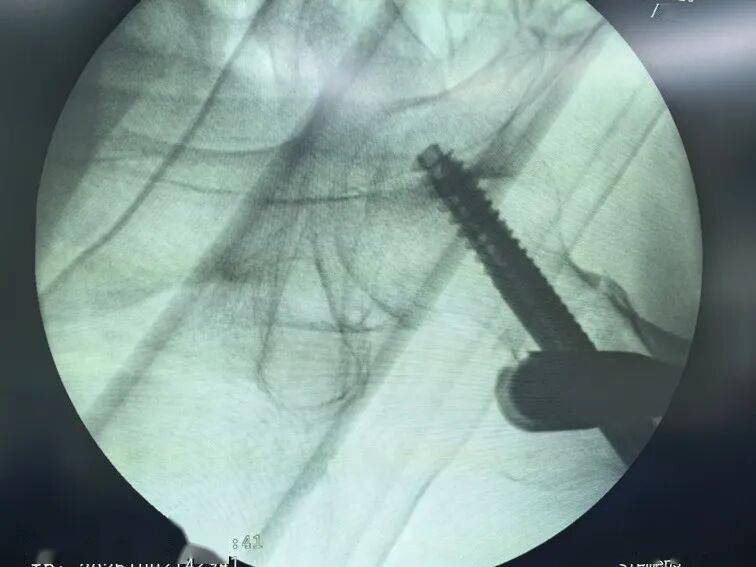

患者术后影像资料

广东省中医院珠海医院急诊科医生为老人迅速完成检查,发现左侧股骨粗隆间骨折,立刻启动老年髋部骨折绿色通道,迅速完善术前检查,并请麻醉科、心内科、ICU等专科会诊和指导治疗,排除手术禁忌症后,在MDT团队检验科、影像科、输血科、超声科等协助下,完成术前准备工作,老人于2日中午被送入手术室并完成手术,此时距离老人受伤还不到24小时。经过5天的良好康复治疗,老人病情稳定,顺利出院。